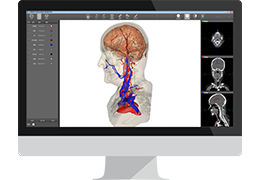

View X-Ray CT & MRI Scans Fast and Easily

Designed for surgeons, Pro Surgical 3D makes it easy to view patient scans quickly. Pro Surgical 3D facilitates the optimal 3D treatment and assessment workflows based on X-ray CT and MRI scans – and best of all, it’s FREE!

High-quality and fast 3D reconstruction and 3D rendering

Performs 3D reconstruction and volume rendering.

Multi-planar slicing.